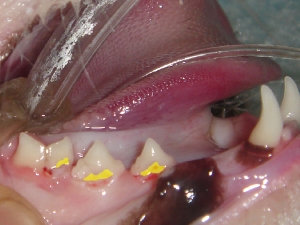

歯石除去 例1

黄色のラインにて歯槽骨をトレースしております。このトレースラインにより、4番と5番の間は歯周病による50%歯槽骨の融解が認められることがわかります。その他の部位に関しましてはほぼ正常です。

黄色:歯周病により退縮した歯肉のライン

赤色:フラップ術における切開ライン。

黄色のラインで示されるような歯肉退縮はしばしば見受けられます。これは歯石をとってもルートプレーニングをおこなってもなかなか正常なラインには戻ってきません。このような場合に、フラップ術を用い、赤色のラインで切開し、歯肉を正常な位置までもどし、再度縫合しなおします。写真黄色の部分をよく観察していただくと実際には、犬歯歯肉を形成しているのは、正常な歯肉ではなく、頬粘膜が引っ張られたような状態であることがわかります。